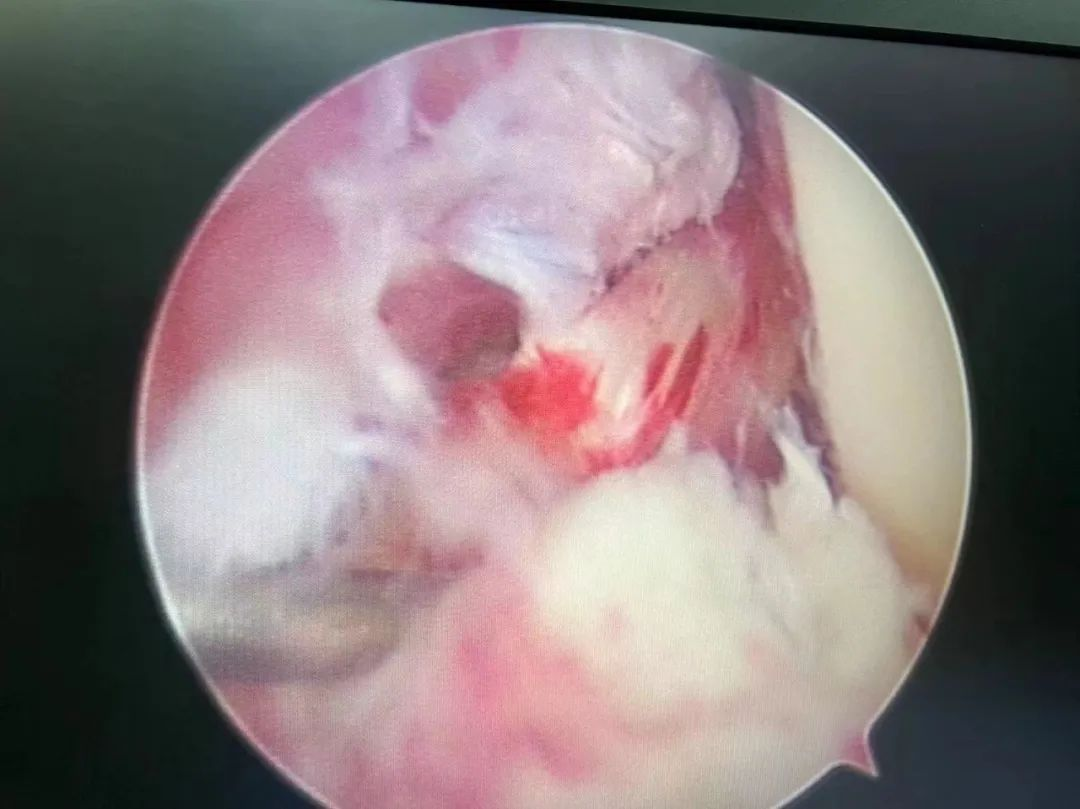

术中镜下观

在骨科陈子华主任、曾红生副主任医师及关节运动医学团队结合患者入院后膝关节MRI及术前MRI,左膝前后交叉韧带断裂诊断明确,考虑到患者术前已制动1月余,手术后不适合长时间限制运动,最终选择人工韧带(LARS)重建前后交叉韧带。采用关节镜微创手术,术中透视见挤压钉固定位置准备,仅用5个微创小切口就为患者完成了手术,出血约为10ml。术后第一天患者就可使用CPM机进行功能康复训练,术后5天患者可屈膝到90°,1周扶拐杖行走,2周非负重行走,顺利出院。